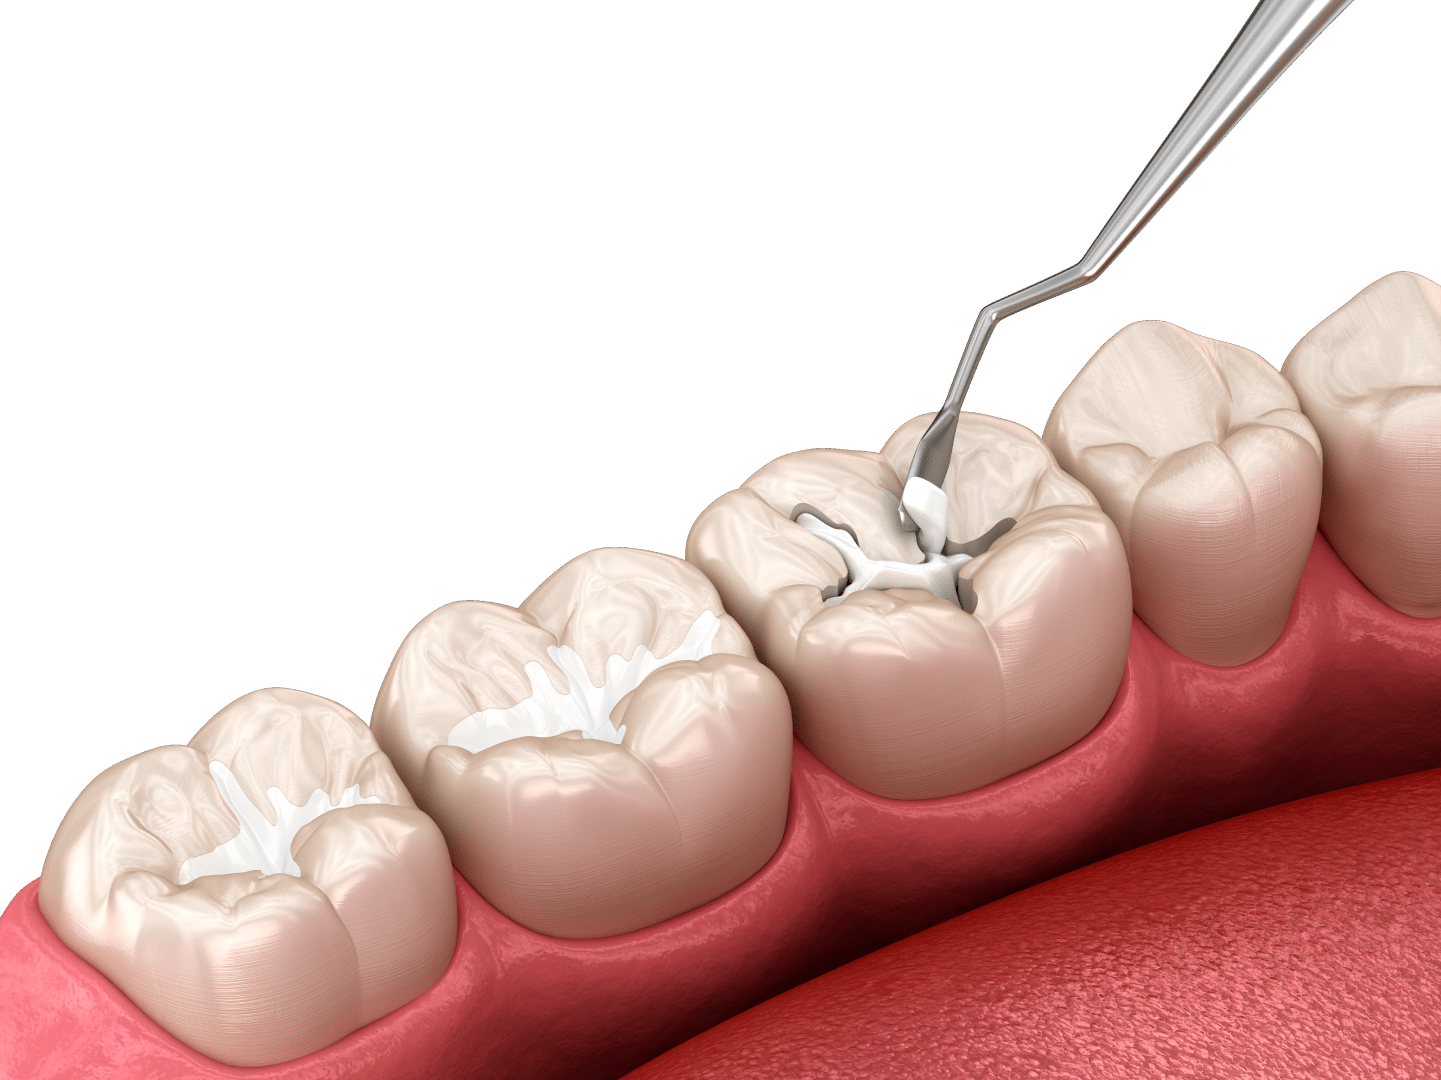

Як відбувається протезування металокерамікою

Металокерамічні коронки в клініці ЦІС зазвичай встановлюються за 2–3 візити до стоматолога. Процедура складається з декількох етапів.